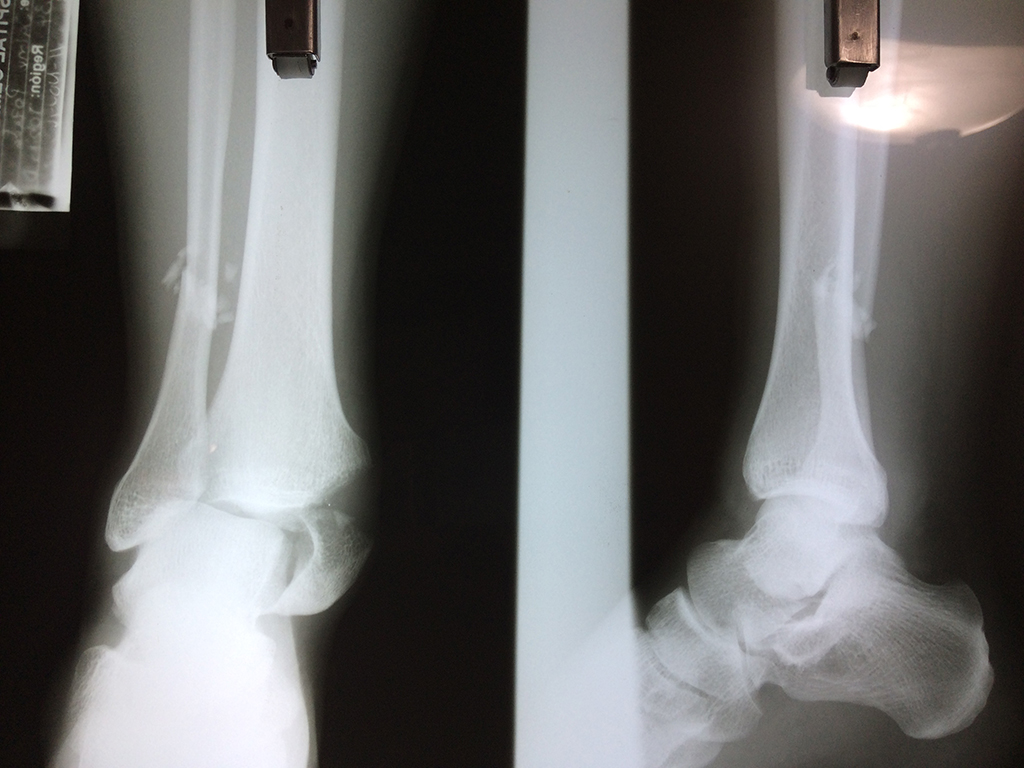

Una fractura de tobillo es la rotura de uno o más de los huesos del tobillo. Estas fracturas pueden ser:

- Parciales (el hueso está sólo parcialmente fisurado, no del todo).

- Completas (el hueso está perforado y está en 2 partes).

- Producirse en uno o ambos lados del tobillo.

Algunas fracturas de tobillo pueden requerir cirugía si:

- Los extremos de los huesos están desalineados entre sí (desplazados).

- La fractura se extiende hasta la articulación del tobillo (fractura intra-articular).

- Los tendones o ligamentos (tejidos que sujetan los músculos y los huesos entre sí) están rotos.